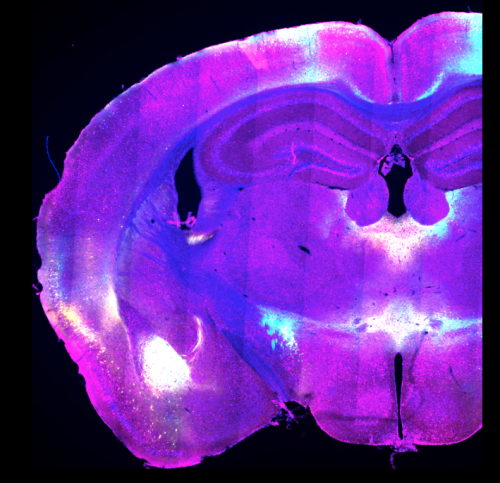

Lo studio è stato condotto durante il periodo post-dottorato che la ricercatrice ha svolto nei laboratori di Losanna: il team ha scoperto le regioni specifiche nel cervello dei topi responsabili della riprogrammazione dei ricordi traumatici, notando che esse sono effettivamente diverse a seconda che il trauma sia avvenuto di recente o molto tempo prima, e ha osservato che potevano facilitare la diminuzione dei sentimenti di ansia e stress associati ai ricordi traumatici di lunga durata migliorando l'attività di una regione primitiva del cervello chiamata nucleo reuniens.

“I ricordi traumatici sono così carichi emotivamente che sono difficili da “cancellare” o estinguere. Nonostante questo, sorprendentemente si sa poco di come il cervello sia in grado di immagazzinare e richiamare alla memoria questi ricordi traumatici anche molti anni dopo. In questo studio, è la prima volta che qualcuno ricerca l'estinzione della paura a livello del circuito cerebrale per ricordi traumatici di lunga durata”, spiega Bianca Silva. “Eravamo particolarmente interessati a studiare i ricordi traumatici cosiddetti “remoti”, cioè risalenti ad un lontano passato, perchè essi sono i più difficili da eradicare e sono frequentemente la causa di disturbo da stress post traumatico”. Il nucleo reuniens del talamo è dunque l’area cerebrale che permette la diminuzione del carico emotivo dei ricordi traumatici a lungo termine.

La ricercatrice spiega anche come il team è arrivato a questo risultato: “Un topo traumatizzato esprime la sua paura restando immobile. Dopo varie sessioni di terapia da esposizione in cui il topo rivive il ricordo di paura in un contesto rassicurante, il topo riacquista sicurezza e mobilità normale. In questo studio, un gruppo di topi ha ricevuto la terapia 1 giorno dopo il trauma, mentre un altro gruppo ha ricevuto la terapia 30 giorni dopo.Gli scienziati hanno determinato quali circuiti cerebrali erano attivi in entrambi i gruppi di topi. Hanno scoperto che 1 giorno dopo il trauma era attiva una via cortico-amigdalare diretta, ma dopo 30 giorni era attiva una via indiretta, radicata nel nucleo reuniens”. “E’  interessante notare che l'attività nei reuniens raggiunge un picco poco prima che il topo smetta di esprimere paura. È come se l'attività nei reuniens anticipasse la fine dell’immobilità: quando abbiamo manipolato l'attività dei reuniens, abbiamo visto che era davvero importante per regolare la paura. Potenziando, infatti,  l'attività di questi neuroni, i topi esprimevano meno paura, mentre quando l'abbiamo inibita, i topi ne esprimevano di più".